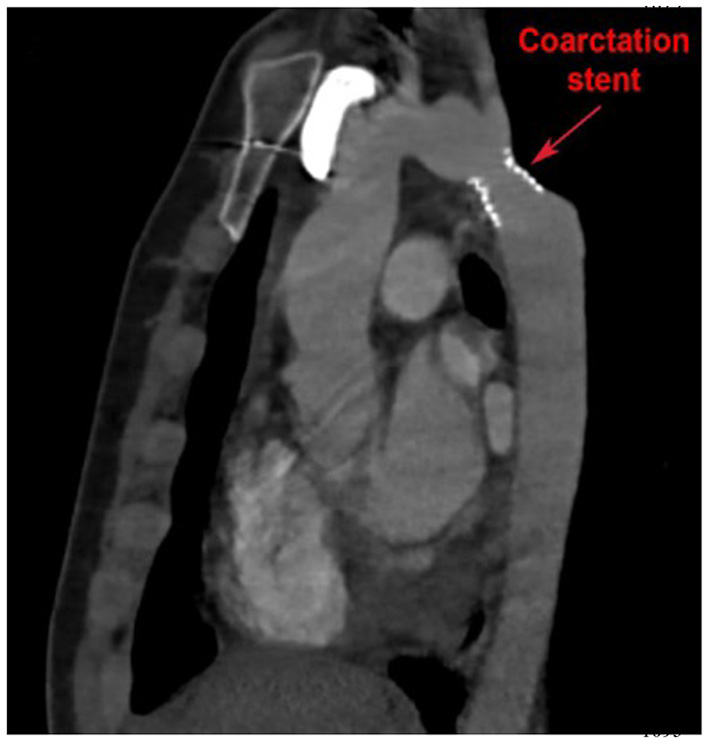

Longitudinal surveillance of isolated CoA includes regular physical examination and interval imaging of the aorta for recurrent CoA. CTA offers a high-resolution 3D assessment of the thoracic aorta. It can be safely utilized in patients with pacemakers and is generally less sensitive to artifact from implanted devices. CTA can be used to evaluate “in-stent” stenosis in patients who have undergone percutaneous stent implantation to treat isolated CoA (Figure 5). Exposure to ionizing radiation is limitation of CTA, although technological advancements have resulted in significant radiation dose reduction, and functional assessment to quantify blood flows and velocities is limited in CTA.

Figure 5

Cardiac computed tomography (CT) imaging of isolated CoA following stent implantation. Cardiac CT also allows for high resolution imaging of the entire aortic arch and enables visualization of possible in-stent stenosis.